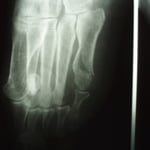

〇第五中足骨骨折

内科で貧血を起こし転倒 安静後立ち上がることができたので帰宅

翌日痛みを訴え来院されました。明らかに骨折の疑いがあるのっで

レントゲン検査を依頼し骨折を確認しました。

病院では通常長靴のようなギプスを巻き、週ごとに骨の状態をレントゲン検査して経過観察していきますが、高齢で足元も不安定なので簡単な副子(あてがう物)と包帯で固定しました。

毎日来院してもらい患部を清潔にし超音波と軽擦(軽くマッサージをして浮腫をとる)をしました。経過良好です。